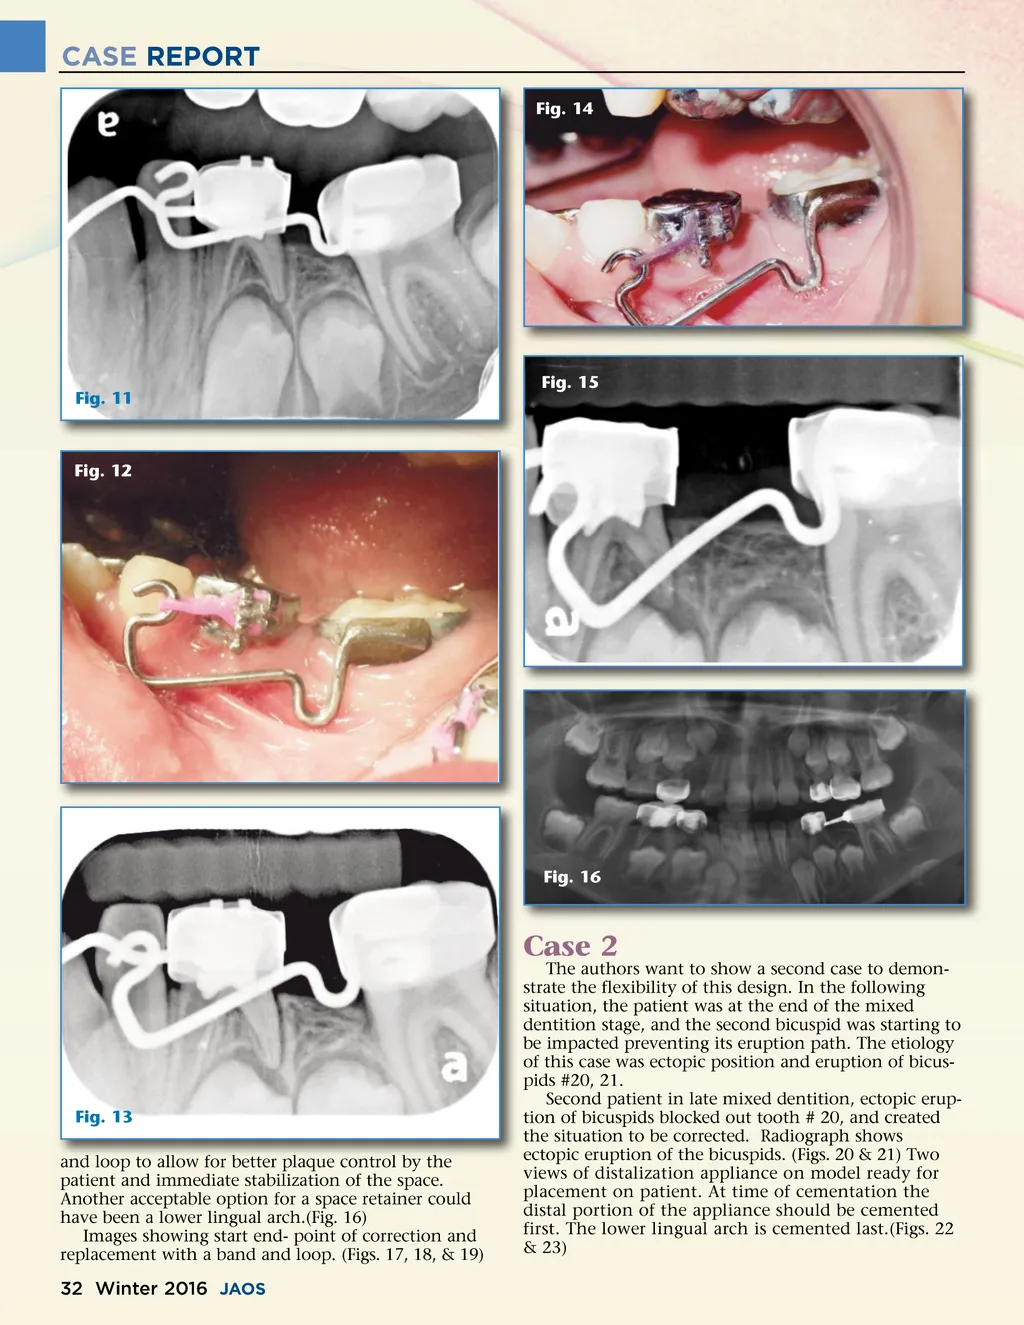

CASE REPORT Fig. 14 Fig. 11 Fig. 15 Fig. 12 Fig. 16 Fig. 13 and loop to allow for better plaque control by the patient and immediate stabilization of the space. Another acceptable option for a space retainer could have been a lower lingual arch.(Fig. 16) Images showing start end-point of correction and replacement with a band and loop. (Figs. 17, 18, & 19) The authors want to show a second case to demon-strate the flexibility of this design. In the following situation, the patient was at the end of the mixed dentition stage, and the second bicuspid was starting to be impacted preventing its eruption path. The etiology of this case was ectopic position and eruption of bicus-pids #20, 21. Second patient in late mixed dentition, ectopic erup-tion of bicuspids blocked out tooth # 20, and created the situation to be corrected. Radiograph shows ectopic eruption of the bicuspids. (Figs. 20 & 21) Two views of distalization appliance on model ready for placement on patient. At time of cementation the distal portion of the appliance should be cemented first. The lower lingual arch is cemented last.(Figs. 22 & 23) Case 2 32 Winter 2016 JAOS